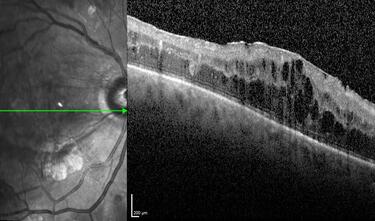

Clase 1 - Conceptos esenciales en fisiología y anatomía de la retina

Clase 3 - Más allá de la interopretación de OCT estructural papilar. Correlación histológica

Clase 15 - Depósitos y signos específicos en DMAE no neovascular

Clase 16 - Distrofia hereditarias de la retina que simulan DMAE no neovascular

Clase 18 - Signos estructurales diferenciales entre neurodegeneración y exudación en DMAE

Clase 20 - Signos clave en patología traccional vítrorretiniana

Clase 21 - Desprendimiento de vítreo y desprendimiento de retina